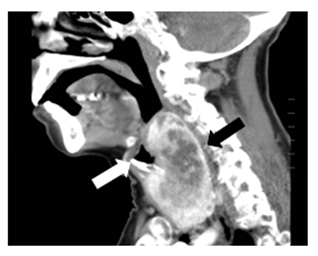

Laboratory testing reveals a TSH 1.14μU/mL (0,35-5,28). Chest radiography does not show tracheal deviation. Gastroscopy does not present esophageal alterations. Cervicothoracic CT shows a multinodular goiter with posteromedial spreading of both lobes that compress faryngoesophageal union and proximal esophagus (black arrows in Figures 1 and Figure 2). Also, larynx and trachea are displaced forward (white arrows in Figures 1 and Figure 3). Right thyroid lobe measures 5,2x4,9x7,8cm. Left thyroid lobe measures 5,7x4,9x8,8cm. Patient is dismissed for surgery due to high anesthetic risk. Currently, patient tolerates turmix diet and fluids with thickeners. Although isolated dysphagia is an uncommon symptom in compressive goiters, whose main manifestation is dyspnea, it is important to rule out an enlargement of the thyroid gland as a cause of dysphagia even in the absence of dyspnea, dysphonia or visible goiter.

Figure 3